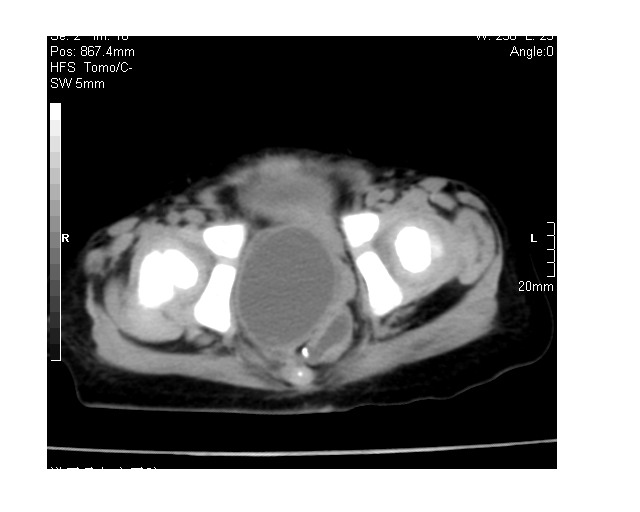

以下是引用lkc8963在2008-3-16 12:49:00的发言:[br]盆底巨大混杂密度肿块,富含多种组织成分包括脂肪/液体/软组织/钙化,边界清楚,向前压迫肠管及膀胱,向后突入骶尾部皮下脂肪层,首先考虑畸胎瘤,诊断时需要与脊柱裂/囊性淋巴管瘤等区别。